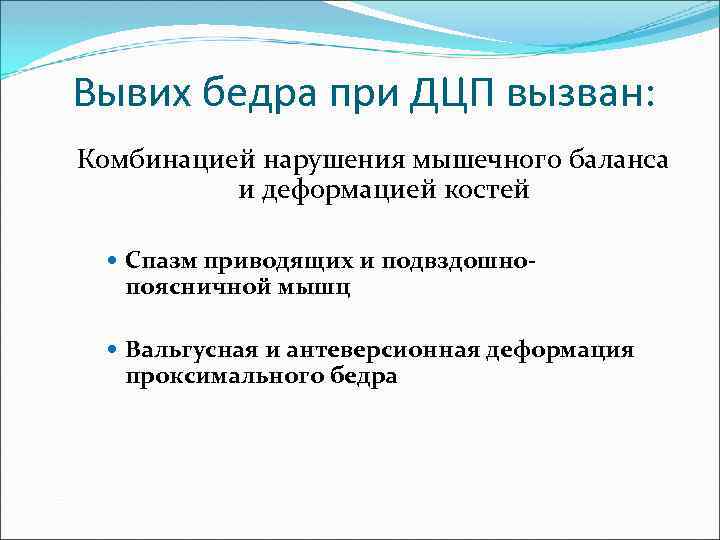

Вывих бедра при ДЦП вызван: Комбинацией нарушения мышечного баланса и деформацией костей Спазм приводящих и подвздошно- поясничной мышц Вальгусная и антеверсионная деформация проксимального бедра